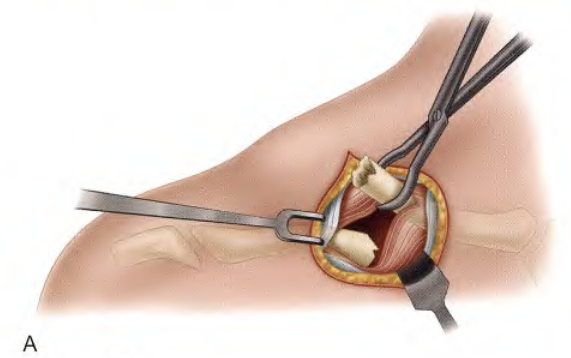

经切口使用巾钳将内侧锁骨的远端抬高。

提起锁骨内侧端

经切口将锁骨外侧端抬高,并外旋手臂和肩关节帮助显露。

-